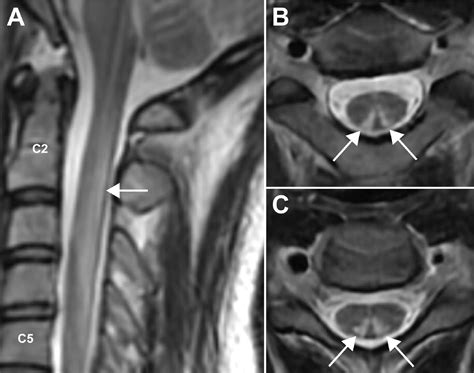

• MRI of the Spine: An MRI can reveal the classic "inverted V" sign in the posterior columns of the cervical spinal cord, which is highly indicative of SCD.